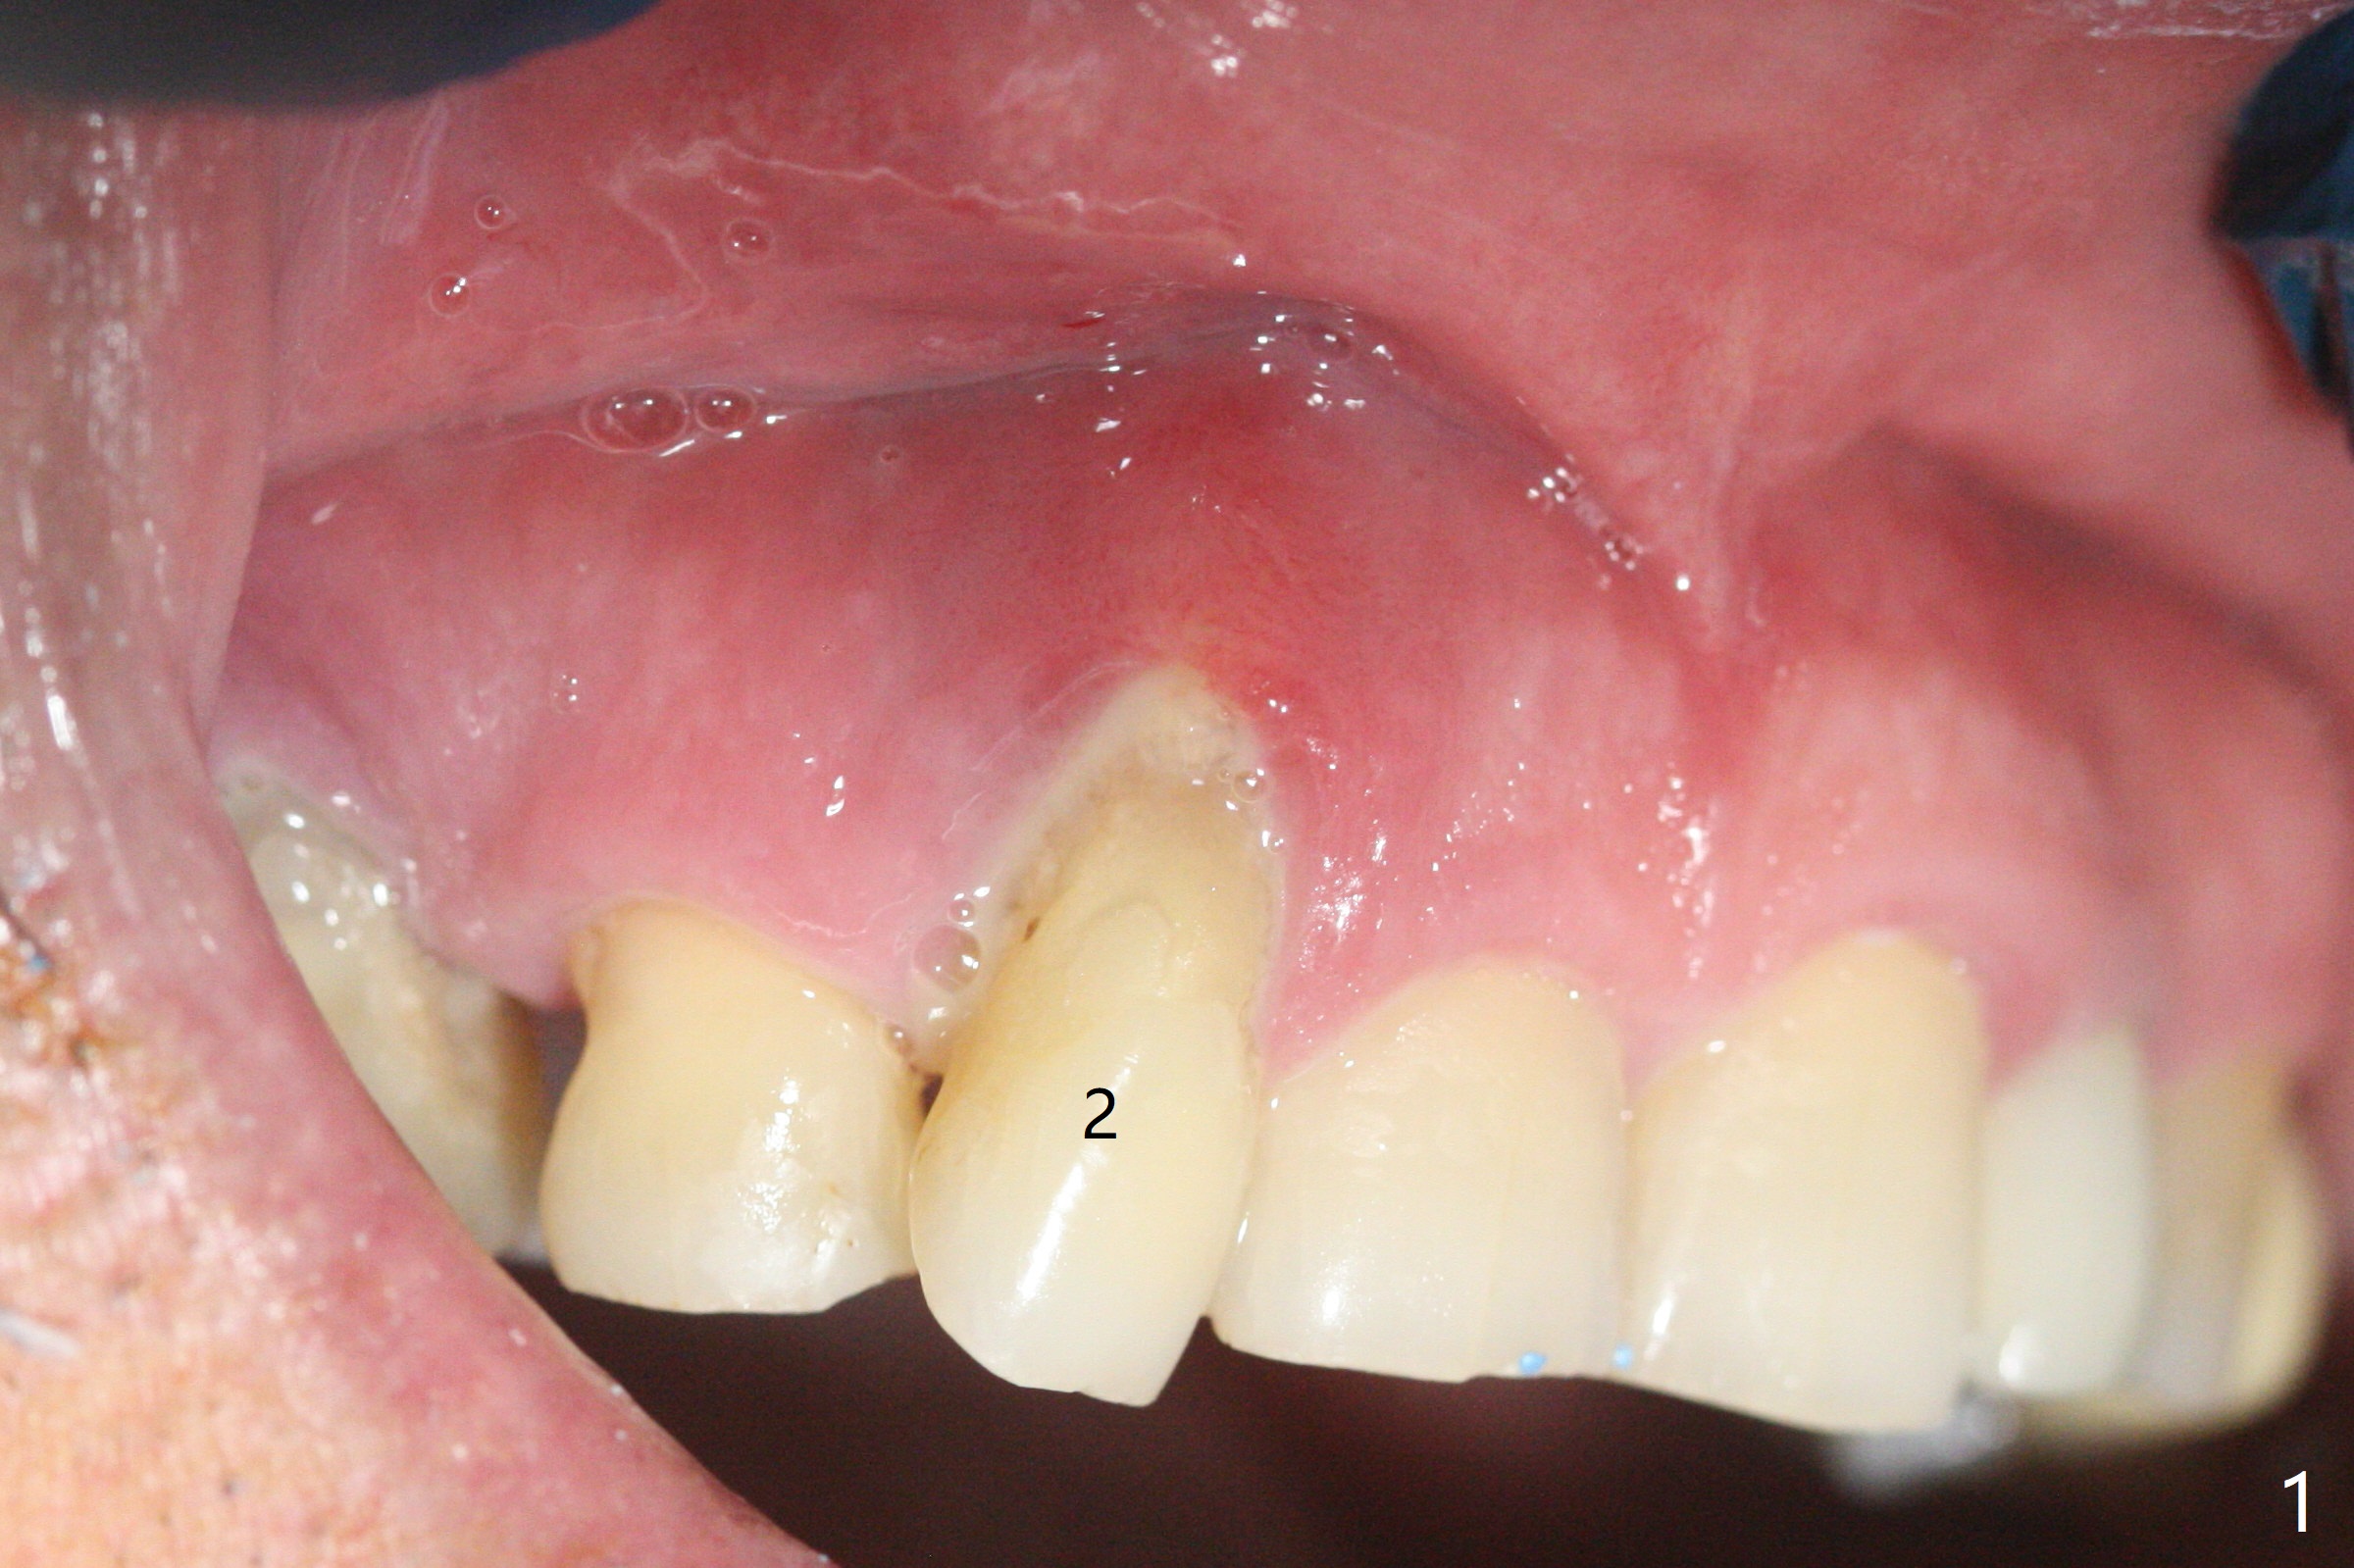

68岁男士右上2严重骨质吸收,颊侧骨板缺失,术前牙龈退缩也十分明显(图一,二),术中对脆弱牙龈缘(图三:*)不应施加任何压力或者牵拉,更不能切开,保持最佳血供。按照术前设计,在牙槽窝腭侧钻洞(图四),植入2.5x15毫米一段式植体(扭力>35Ncm),基台特长(牙龈厚,图五)),基台位于合适修复位置(图六),4-5毫米螺纹颊侧暴露(图七:*)。植骨(图八(CT冠状切面(拔牙后:黑色)):箭头)前,将PRF膜(白线)一头(a)插入牙槽窝颊侧,另外一头(图八,九:b)放置颊侧牙龈颊侧。然后填入粘性骨粉(图九:S;图十四:*),将b头PRF膜往下翻,它末端事先冲一个洞(punch a hole using sterilized rubber dam punch),插入基台(图十(粉红色),十一),这样PRF膜不移位,牢靠地固定骨粉(图十(红圆圈),图十四:*),最后使用树脂敷料覆盖伤口(图十二,十三:A),同样需要基台(箭头,也就是一段式植体)固定,也就是没有即刻植体,就没有骨粉固位。术后两个月伤口缩小,肉芽组织生长(图十五)。撤除树脂敷料后,制作临时牙冠,半个月后唇侧植体有些暴露(图十六),嘱咐强化口腔卫生。